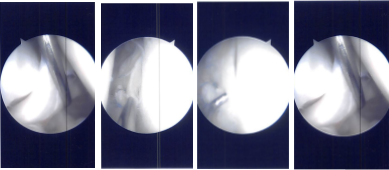

Intraoperative Arthroscopy Images

The intercondylar area was examined and the acromioclavicular ligament was found to be intact. The lateral femoral condyle was examined, and the lateral meniscus was intact. There was no cartilage damage on the lateral femoral condyle.

Now the repair of the bucket-handle tear of the posterior horn of the medial meniscus was started using FasT-Fix. Four FasT-Fix were used and taking bite, the peripheral and then the central part of the meniscus was performed.

The suture was cinched and tightened to find the good reduction of the tear. The tear was opposed well after the use of the four FasT-Fix. The chondroplasty of the patella was also done. The knee was irrigated and washed.

Intraoperative Arthroscopy Images

The scope was moved to the intercondylar area where ACL was found to be intact. Partial synovectomy was performed in that region. The scope was moved to the lateral femorotibial compartment where the left meniscus was intact. no chondral damage to the lateral femoral condyle.

Then, the scope was reentered into the patellofemoral joint where the trochlea was found to have grade 1 condylar lesions. No chondroplasty was performed on the trochlea. There were grade 2 to grade 4 lesions on the inferomedial patella facet. Chondroplasty was performed.

Now, the scope was moved from the lateral to the medial working portal. The lateral working portal was clean and using a shaver to make easy access to the medial meniscus.

Zone specific cannulas were reused to pass sutures through the medial posterior horn and body of the medial meniscus through the capsule. Three horizontal and one vertical mattress suture were used. They were held firmly and found to have made a good reduction of the meniscus